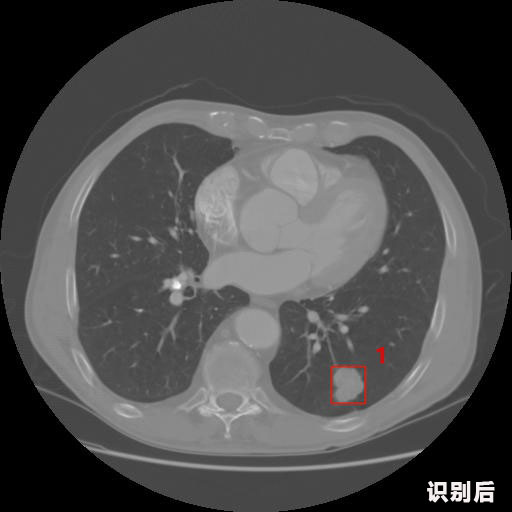

英特健康AI深度學習醫(yī)療圖像識別系統(tǒng)案例_胸部CT

1.發(fā)現(xiàn)肺結(jié)節(jié)的可能性為95.56%---位于框指數(shù)位置:[331.70554 366.13406 365.21707 403.96234]